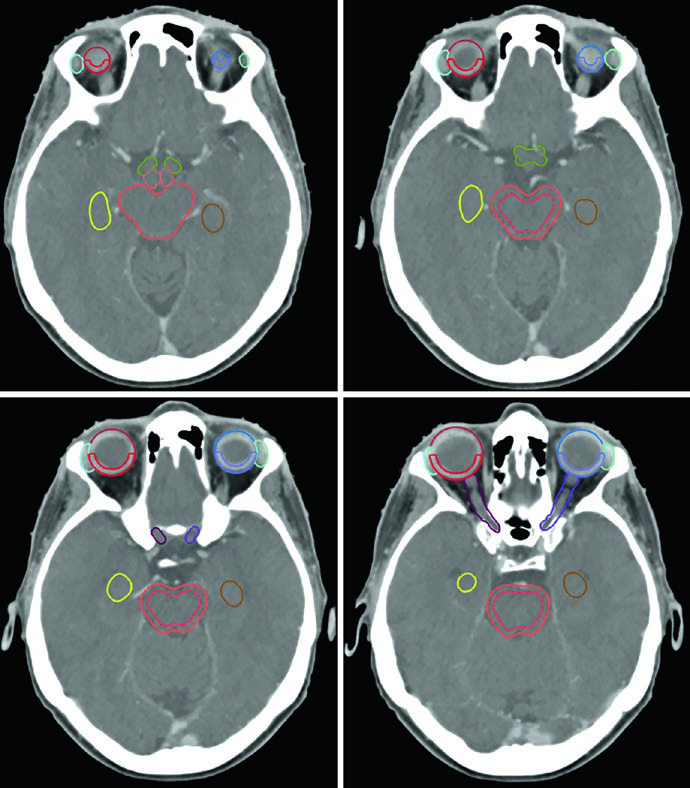

La lista de estructuras normales a contornear es extensa. Para la mayoría de los tumores cerebrales primarios benignos, los OARs incluyen: encéfalo completo, encéfalo no involucrado (encéfalo menos GTV o CTV según el escenario), tronco encefálico dividido en core y superficie (anillo periférico de 3 mm), médula espinal, cócleas bilaterales, globos oculares, cristalinos, nervios ópticos, quiasma óptico, retinas, glándulas lagrimales, lóbulos temporales, hipocampos, hipotálamo y glándula pituitaria. Los volúmenes de riesgo planificado (PRVs) pueden crearse para tumores adyacentes a estructuras críticas, facilitando la evaluación dosimétrica.

Cada OAR tiene una ventana de visualización óptima. El tronco encefálico, quiasma óptico y componentes intracraneales de los nervios ópticos se ven mejor en ventana cerebral. Los nervios ópticos en los canales ópticos y sus componentes orbitarios son más nítidos en ventana de partes blandas. Las cócleas solo se identifican con precisión en ventana ósea — y según la posición de la cabeza, pueden no encontrarse en el mismo corte axial. El hipocampo — específicamente la zona subgranular — se delinea en T1 de RM y se visualiza como sustancia gris hipointensa, desde el nivel donde limita con el atrio del ventrículo lateral superiormente hasta la extensión inferior del cuerno temporal.

Un punto práctico fundamental: la evaluación por TC es esencial para decidir si los cambios periósticos y óseos deben incluirse en el GTV. En el ejemplo del meningioma del seno cavernoso (Figura 29.7), el tumor fue delineado con RM de planificación, recibió margen de 2 mm para el PTV y fue tratado a 52,2 Gy en 29 fracciones. Las líneas de isodosis muestran conformación estrecha alrededor del tronco encefálico, quiasma, nervios craneales adyacentes, arteria carótida y cóclea derecha.

Los meningiomas selares y supraselares voluminosos con resección incompleta — como en la Figura 29.8 — pueden requerir expansión de PTV de 3 mm debido a la enfermedad residual extensa. La relación íntima con ambos globos oculares y el tronco encefálico exige una planificación dosimétrica cuidadosa, frecuentemente con IMRT o VMAT para conformar la dosis y proteger estas estructuras críticas.